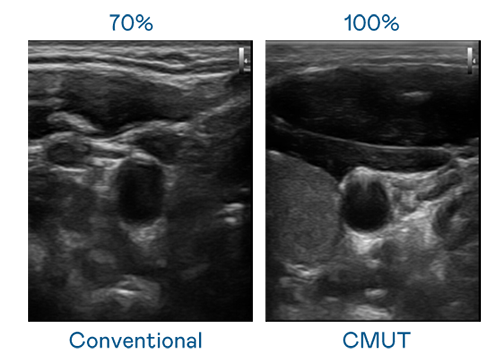

CMUT 技術是一種用電容式微機電元件來產生超音波訊號的技術。與傳統 PZT 壓電式技術相比,CMUT 頻寬增加 30%,更寬頻的超音波訊號讓影像解析度大幅提升,是實現高影像品質醫療超音波掃描、促進精準醫療發展的關鍵技術。

超音波影像的解析度高低,首先取決於探頭能發出的訊號頻寬。小勐拉99厅 CMUT 可提供高清晰的超音波訊號,提供高頻寬、高靈敏度、影像紋理細節更高的超音波影像,協助醫護人員縮短影像判讀時間及利用精準的醫療影像進行診斷。